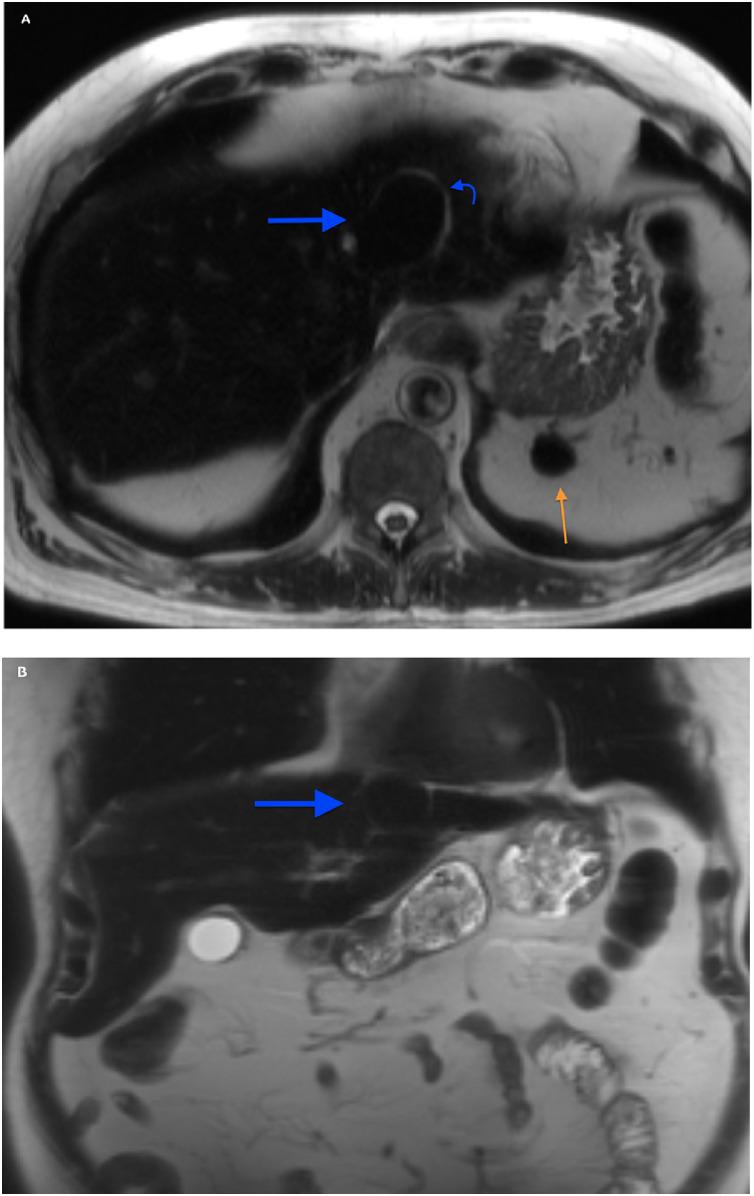

Hepatic splenosis, a rare entity, is the ectopic implantation of splenic tissue into the hepatic parenchyma, most often incidentally seen in patients with a history of splenic trauma and splenectomy. We present a unique case of hepatic splenosis in a patient with hemosiderosis and splenectomy following the incidental finding of hepatic masses on pretransplant imaging. Final diagnosis was made based on cross-sectional imaging characteristics matching that of the left upper quadrant splenules alone. We discuss common characteristics of hepatic splenosis on multiple modalities, the effect of iron deposition on the imaging characteristics of hepatic and splenic tissue and how that impacts the differential and diagnosis. This case highlights the unique imaging characteristics hepatic splenosis can have particularly in the setting of hemosiderosis. Hepatic splenosis imaging diagnosis has a significant advantage over tissue diagnosis in terms of decreased risk, time and cost.

肝脾组织异位种植是一种罕见的疾病,是脾脏组织异位植入肝实质,多见于有脾外伤和脾切除术病史的患者。我们报告了一例独特的肝脾组织异位种植病例,该患者有血色素沉着症且接受过脾切除术,术前移植影像检查偶然发现肝脏肿块。最终诊断基于仅与左上象限脾小结相匹配的横断面影像特征。我们讨论了肝脾组织异位种植在多种检查方式下的常见特征、铁沉积对肝脏和脾脏组织影像特征的影响以及这如何影响鉴别诊断。该病例突出了肝脾组织异位种植尤其是在血色素沉着症背景下可能具有的独特影像特征。在降低风险、时间和成本方面,肝脾组织异位种植的影像诊断相对于组织诊断具有显著优势。